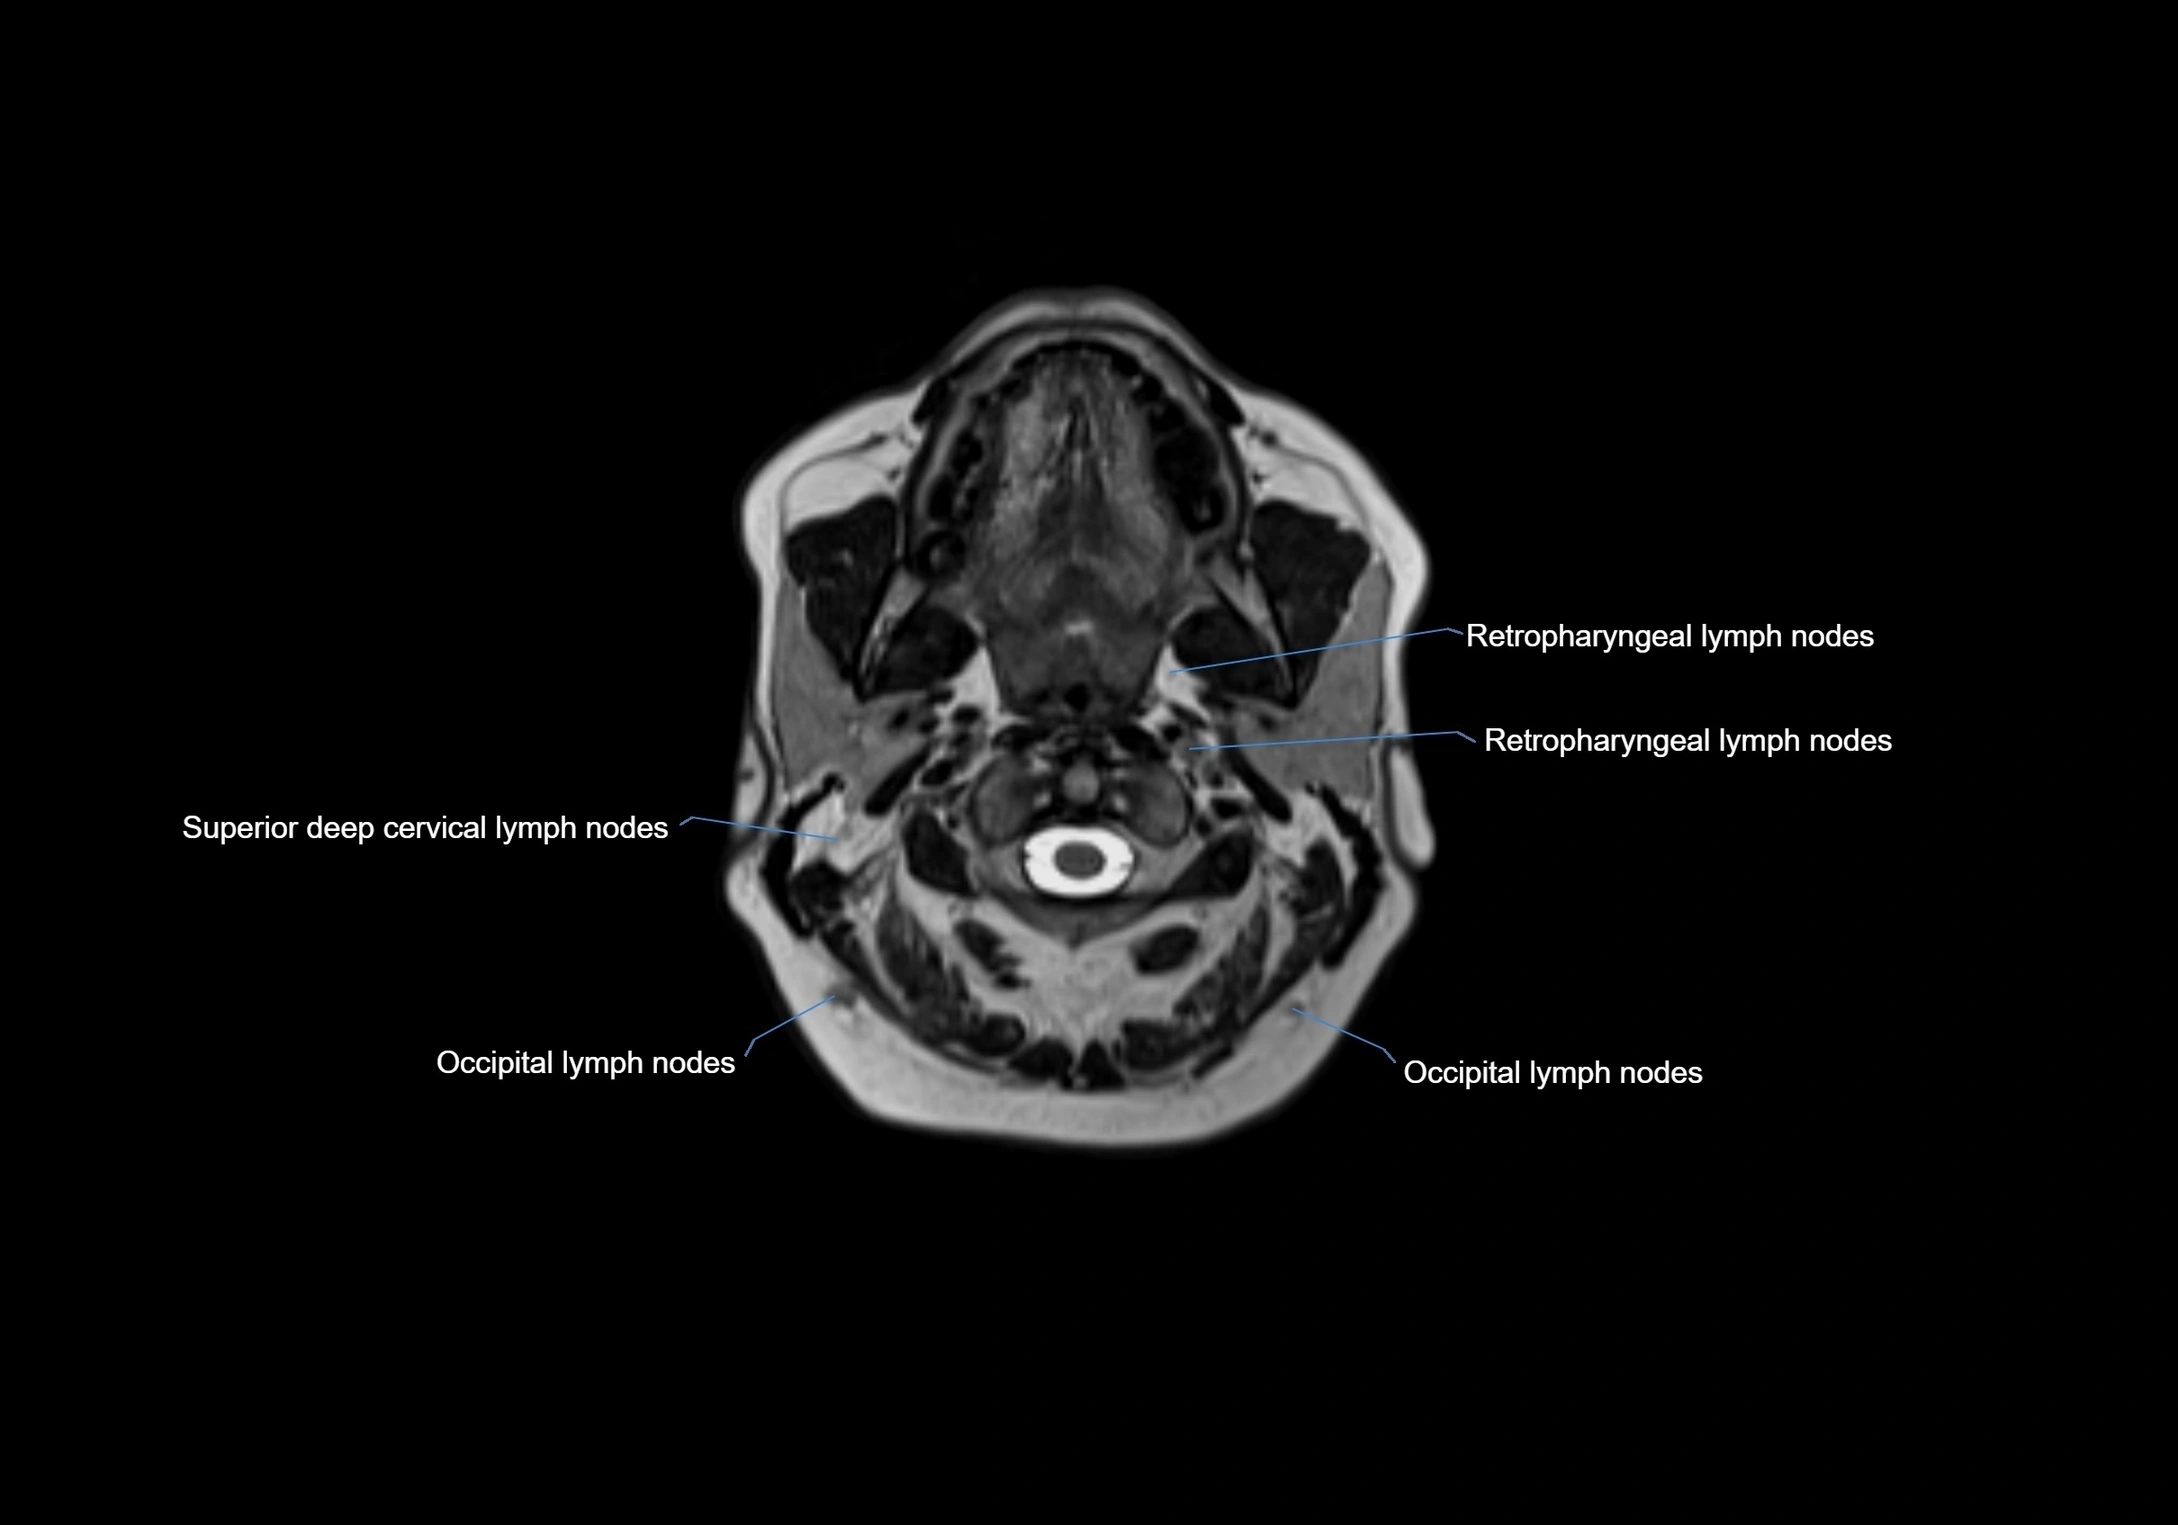

Accessory lymph nodes are small, secondary lymph nodes located along the main facial and cervical lymphatic chains, often adjacent to primary lymph nodes, such as preauricular, submandibular, or occipital nodes. They are typically less than 5 mm in diameter, embedded within subcutaneous fat or connective tissue, and may be variable in number and location. These nodes provide additional filtration and immune surveillance for lymph collected from the face, scalp, and neck regions. Accessory lymph nodes are usually non-palpable in healthy individuals but may enlarge in response to infection, inflammation, or metastasis, making them clinically significant.

Location

• Found along primary lymph node chains, including preauricular, submandibular, parotid, and occipital regions

• Embedded in subcutaneous fat or superficial fascia, often lateral or posterior to primary nodes

• Variable in number; may occur unilaterally or bilaterally, depending on individual anatomy

MRI images